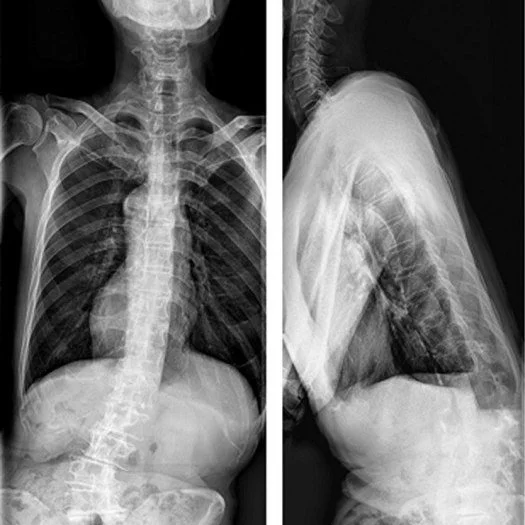

Most people seek chiropractic care for pain relief. But what if your pain, numbness, headaches, or other symptoms are actually secondary conditions – warning signs of an underlying structural problem?

At Structural Chiropractic, we don't just treat symptoms. We identify and correct the Structural Abnormalities that cause them.

We focus on Precision Structural Correction (PSC) – detecting and correcting the structural shifts in your spine that create problems throughout your body.

Your spine works much the same way. When spinal alignment is compromised, it can trigger numerous health issues throughout your body. Treating only the symptoms without addressing Structural Abnormalities won't resolve the root problem and could allow progressive deterioration of your spine over time.